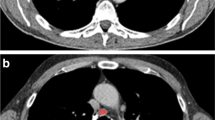

Each lymph node had TA performed on the primary unfiltered image as well as the image after 2-mm spatial scaling filtering (SSF2) to highlight clustered features (Fig. 1). The SSF2 filter performed best among the different filter settings in distinguishing benign from malignant lymphadenopathy (SSF1–6; other data not shown). Malignant and benign lymph nodes demonstrated significantly different TA parameters of mean, SD, MPP and skewness on the unfiltered image data and significantly different TA parameters of mean, entropy, MPP and skewness on the filtered image data (Table 2).

Axial contrast-enhanced CT images show examples of benign (a, right inguinal lymphadenopathy in a 9-year-old boy with Crohn disease) and malignant (b, left cervical lymphadenopathy in a 10-year-old boy with Hodgkin lymphoma) lymphadenopathy with regions of interest (ROI) applied using TexRAD to allow calculation of texture quantification parameters with and without the use of a 2-mm filter. MPP mean value of positive pixels, SD standard deviation